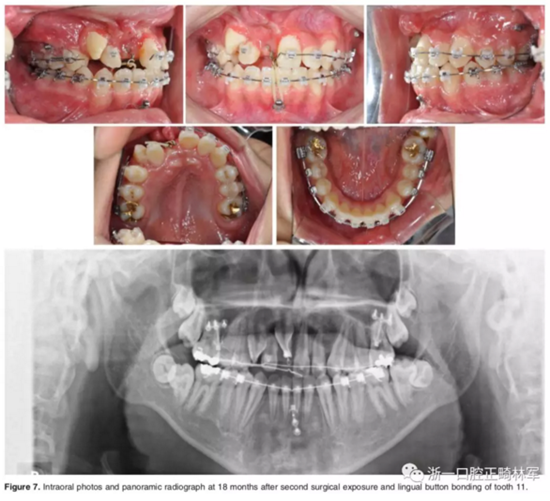

二期手術(shù)主要是牽引中切牙:于上頜前牙區(qū)腭側(cè)作切口,翻全厚瓣,在切牙唇側(cè)粘扣掛結(jié)扎絲牽引;軟組織愈合后,牽引開始。為施加合適的垂直向力,在下頜前牙區(qū)放置C型管,掛橡皮筋牽引。14個月后,切牙牙冠萌出。使用mini管代替托槽,對切牙、尖牙進(jìn)行矯治;矯治過程采用輕力,0.014-in鎳鈦絲。

第三階段:

中切牙旋轉(zhuǎn)矯正后,患者至牙周科醫(yī)生處行右上前牙區(qū)骨增量手術(shù)。前牙區(qū)翻瓣后,使用Bio-oss及膠原膜覆蓋所有骨壁開窗或較薄處,皮瓣復(fù)位縫合。2周后,繼續(xù)進(jìn)行正畸矯治。